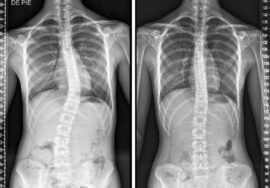

اعوجاج العمود الفقري المراهقي (Adolescent Idiopathic Scoliosis – AIS) هو انحناء جانبي للعمود الفقري غالبًا مع دوران الفقرات. كلمة “مجهول السبب” تعني أن السبب الدقيق غير معروف، ولكن العوامل الوراثية، الهرمونية، والميكانيكية قد تلعب دورًا في حدوث الانحناء.

دراسة حديثة استخدمت الرنين المغناطيسي (MRI) لتقييم شكل وحجم الغضاريف بين الفقرات لدى فتيات مصابات بانحناء صدري أيمن، مقارنة بفتيات أصحاء. النتائج أبرزت عدة نقاط مهمة:

تغير شكل الغضاريف والفقرات

في الفتيات المصابات بانحناءات شديدة، لوحظ اختلاف في زاوية الغضروف وارتفاعه مقارنة بالفتيات الأصحاء، مما يشير إلى تأثير ميكانيكي مباشر للانحناء على شكل الأقراص.تحرك النواة اللبية باتجاه الجهة المحدبة

في الحالات الشديدة، تميل النواة اللبية إلى الانتقال باتجاه الجهة المحدبة للانحناء، ما يزيد الضغط على الأقراص ويعزز تفاقم الانحناء.انخفاض حجم الغضروف والنواة اللبية

كلما زادت شدة الانحناء، لوحظ انخفاض في حجم الأقراص والفقرات المركزية، ما قد يزيد من خطر تآكل الأقراص أو الانزلاق الغضروفي مستقبلًا.ارتباط مباشر بشدة الانحناء

زاوية كوب (Cobb Angle) كانت مرتبطة بشكل مباشر بتغيرات الغضروف والنواة اللبية، مما يؤكد أن الضغط الميكانيكي الناتج عن الانحناء يساهم في تطور الحالة.